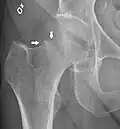

X-ray showing a suspected compressive subcapital fracture as a radiodense line -

CT scan shows the same, atypical for a fracture since the cortex is coherent -

T1-weighted turbo spin echo MRI confirms a fracture, as the surrounding bone marrow has low signal from edema.